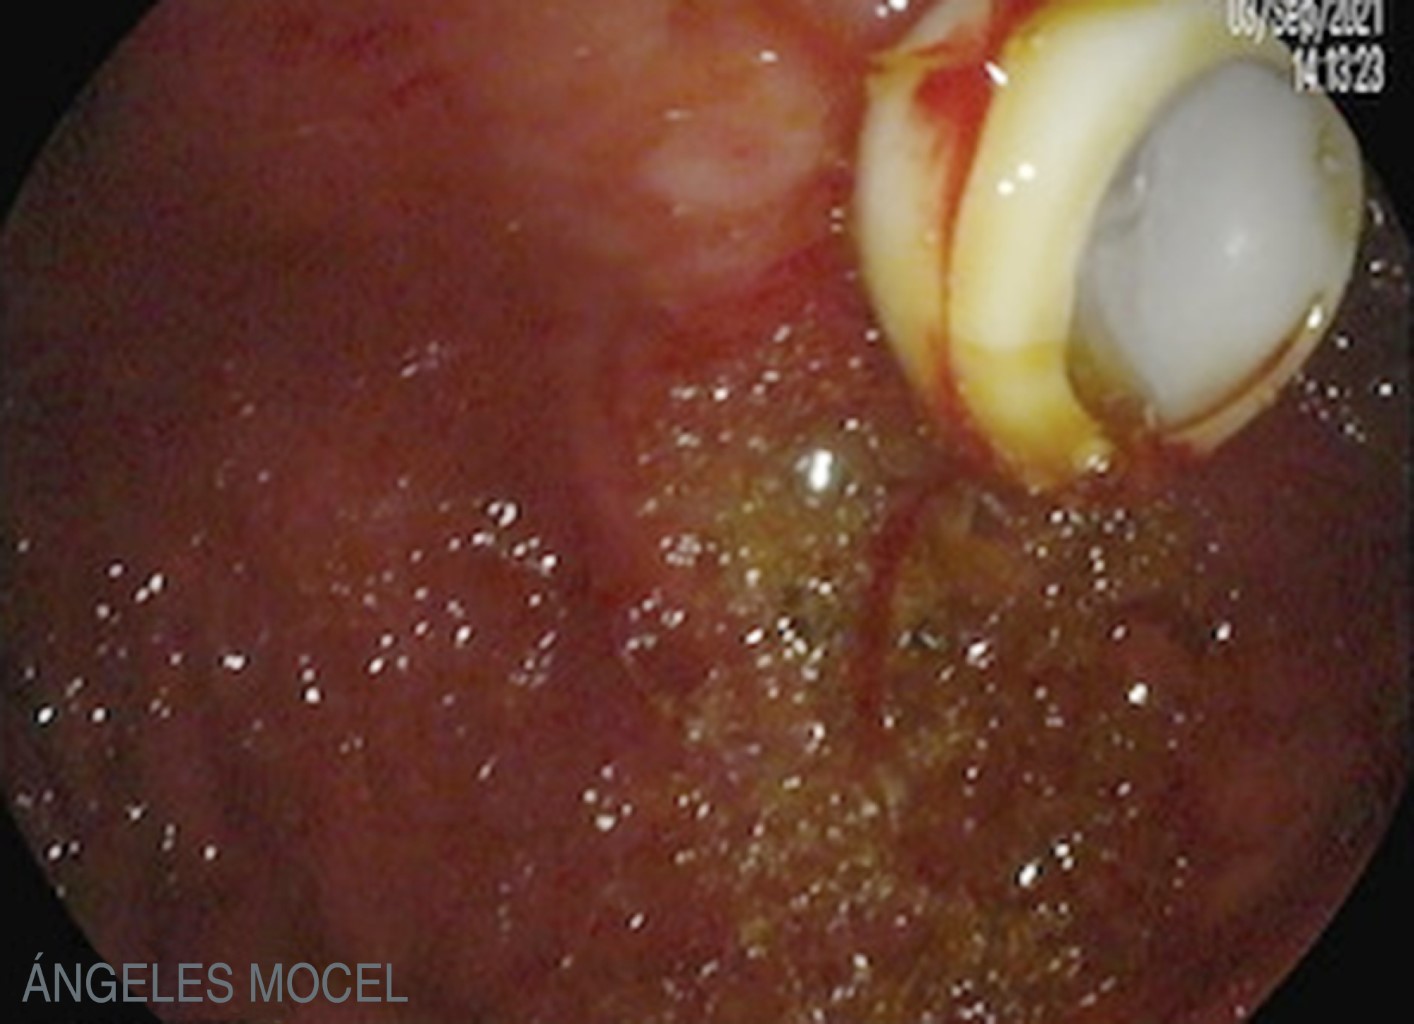

Figure 2